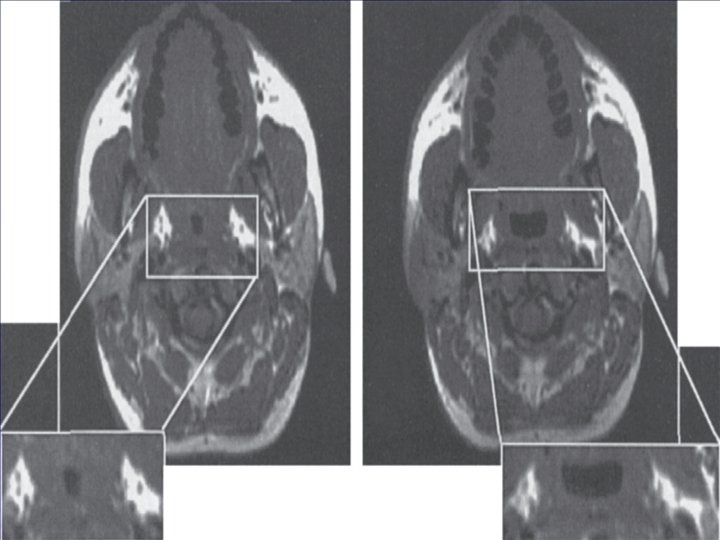

PAP for SDB Studies have shown CPAP to increase upper airway size, especially in the lateral dimension. Positive intraluminal pressure expands the upper airway (pneumatic splint) and increase in lung volume due to CPAP (due to a downward pull on upper airway structures during lung expansion “tracheal tug”), may also increase upper airway size and/or stiffen the upper airway walls, making them less collapsible.